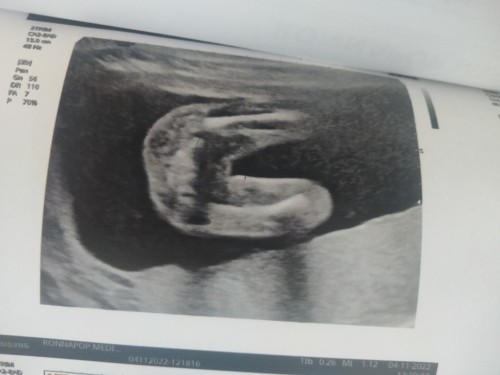

สอบถามแม่ๆค่ะแบบนี้ผู้หญิงไหมคะ

น่าจะผู้หญิงนะคะ อันนี้ของแม่ ได้ผู้หญิงค่ะ

ผู้หญิงค่ะ บ้านนี้ก็แบบนี้เลย